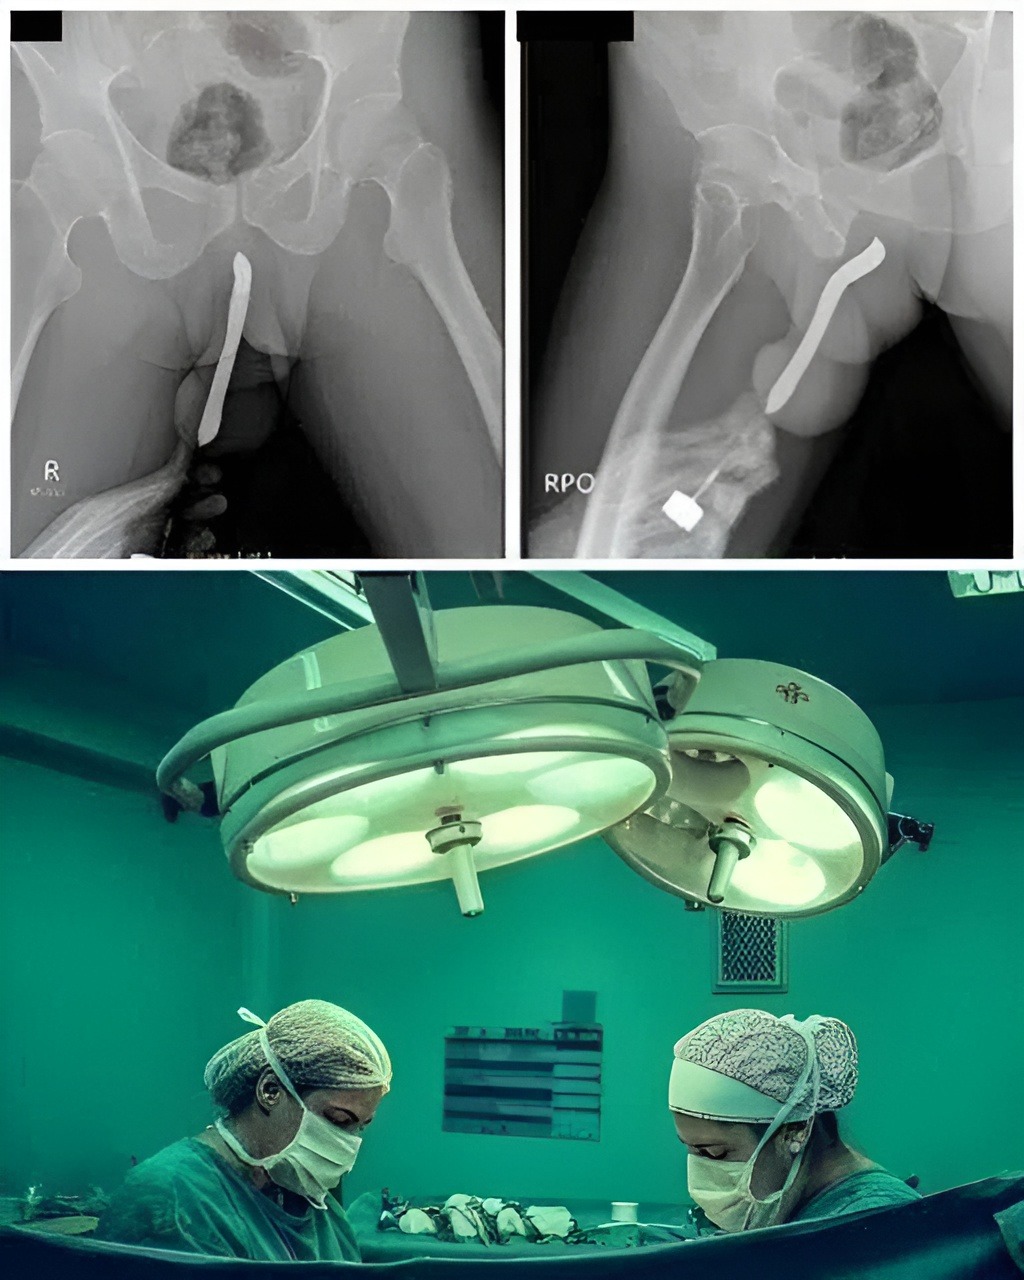

The object caused severe internal injury, leading to pain, bleeding, and the risk of infection. She was taken to the hospital, where doctors performed emergency treatment to remove the object and prevent further complications.

Medical staff were able to stabilize her, but experts said the outcome could have been much worse without urgent care. Serious injuries like this can lead to lasting damage or dangerous infection if not treated quickly.